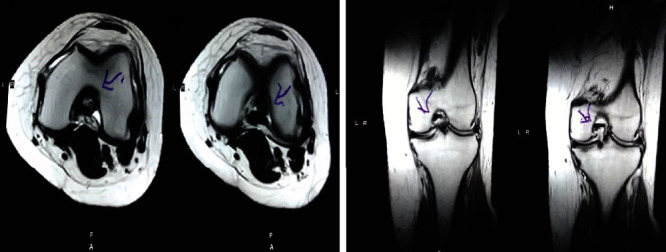

圖2:治療后MRI顯示內(nèi)側(cè)和外側(cè)半月板后角的撕裂有所改善?;颊呓?jīng)歷了癥狀改善以及進(jìn)行日常生活活動(dòng)的能力增強(qiáng)。